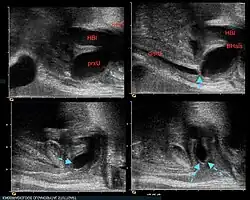

Urethralklappe (blauer Pfeil) im Sonogramm während Miktion. HBl=Harnblase, BHals=Blasenhals, Sym=Symphyse mit Schatten, prxU=proximale Urethra, distU=distale Urethra

Nach der Geburt fallen die Kinder durch einen schlechten „stotternden“ Harnstrahl, im Ultraschall ebenfalls durch eine große Blase, verdickte Blasenwand und Erweiterungen an den Nieren und Harnleitern auf. Der direkte Klappennachweis ist sonographisch gleichfalls möglich.[2] Bei geringer Ausprägung der Klappen können die Kinder erst später durch Probleme beim Trockenwerden oder durch Harnwegsinfekte auffallen.

Die Diagnose wird aufgrund der charakteristischen Wandverdickung mit Unregelmäßigkeiten im Ultraschall gestellt und mittels Miktionszystourethrogramm bestätigt.